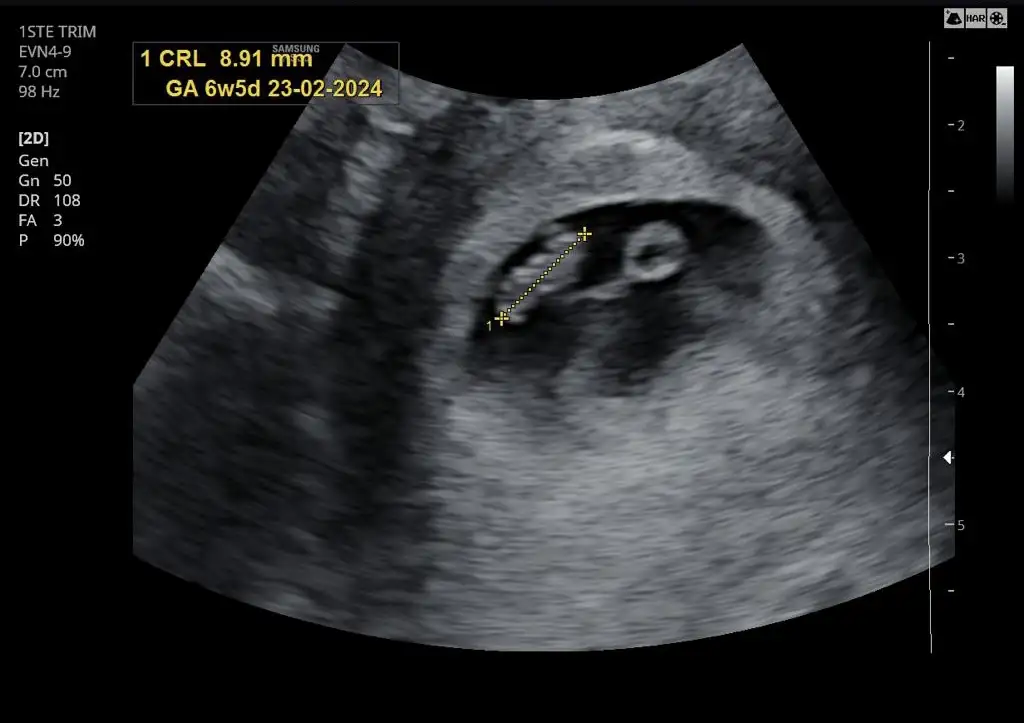

Dayanamiycam ben de sorucam. Vajinal ultrason. Ne diyorsunuz kizlar? Kiz mi erkek mi?

• 8cec3b34-5a7b-4264-abc9-b8a43e88a4e9.webp

8cec3b34-5a7b-4264-abc9-b8a43e88a4e9.webp

25,5 KB · Görüntüleme: 80